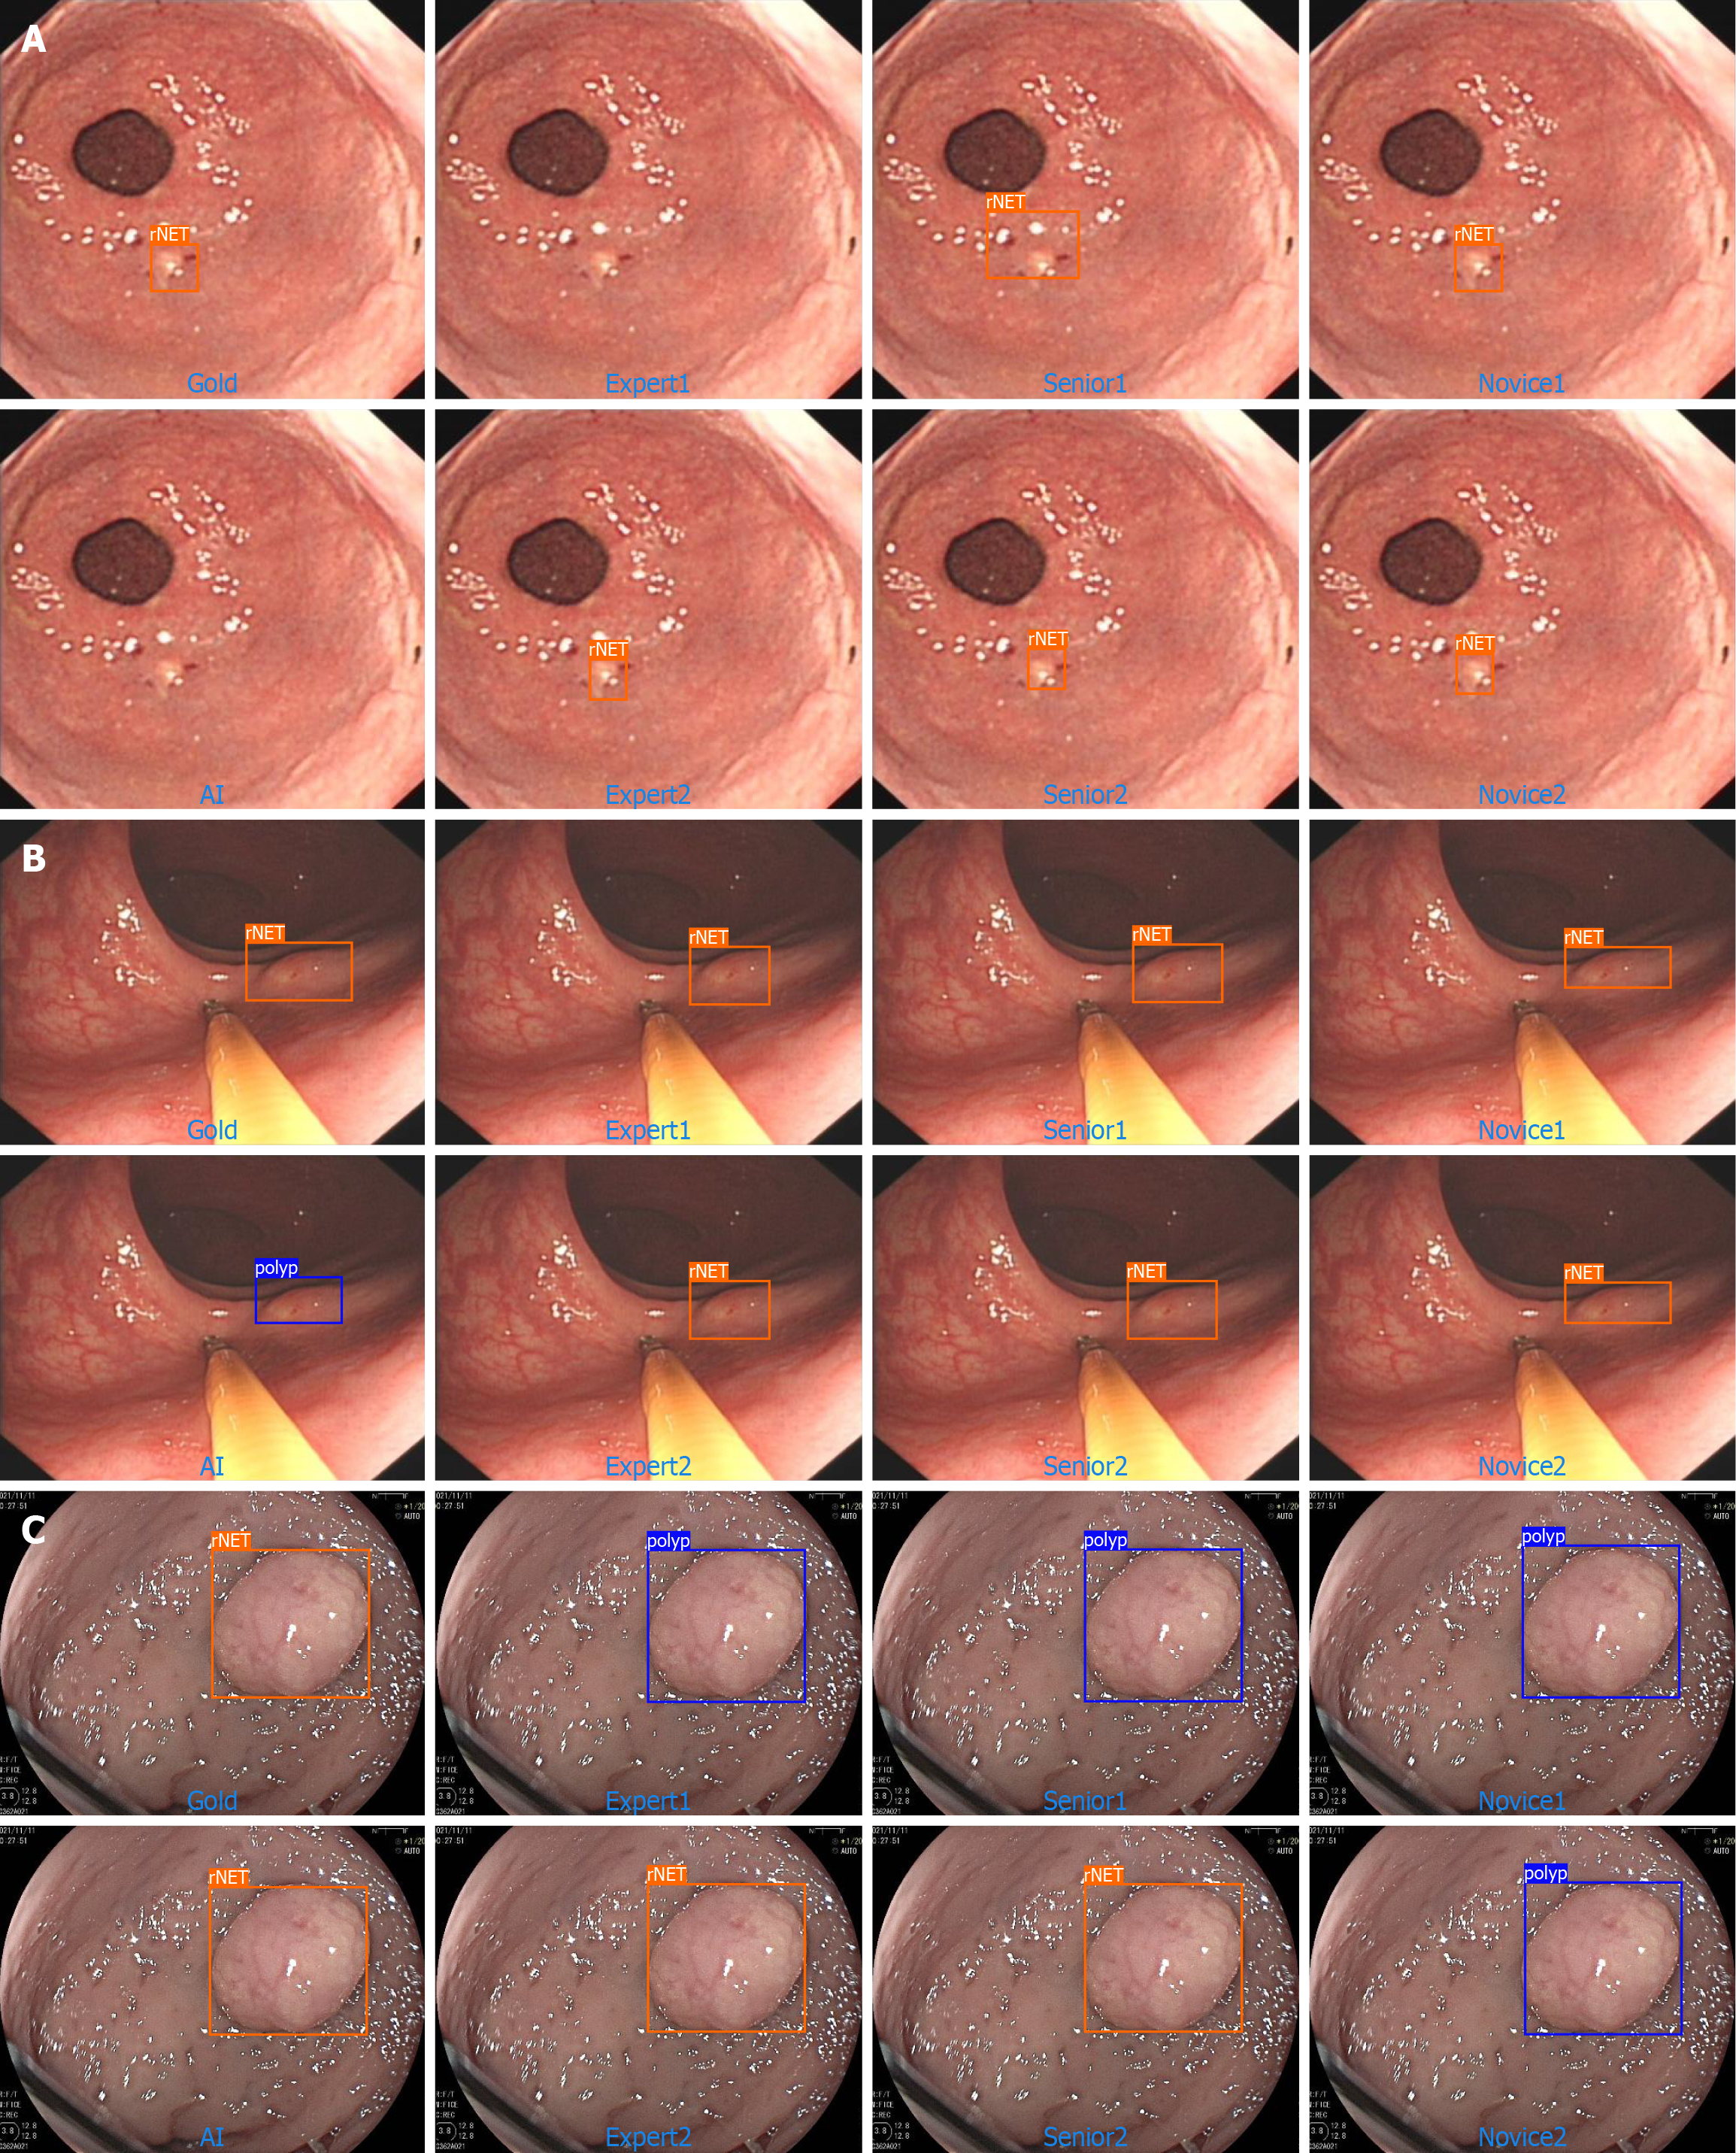

Figure 4 Error both, artificial intelligence, and endoscopist.

A: Error both; B: Error-artificial intelligence; C: Error-endoscopist. rNET: Rectal neuroendocrine tumor.